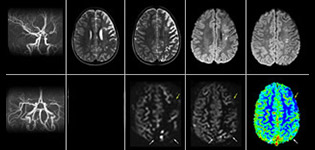

pCASL helps assess brain perfusion without contrast

Pseudo-continuous arterial spin labeling (pCASL) was developed for brain perfusion imaging without contrast agent. “This is very desirable in pediatric patients where the general trend is to limit the administration of contrast,” says Dr. Miller.

Dr. Miller uses pCASL for all patients who present with chronic and acute cerebrovascular abnormalities such as acute stroke, as well as patients who present with signs of acute inflammation in the brain, and occasionally in patients with tumors, to assess the perfusion status of their tumor.

“In combination with diffusion weighted imaging, it can help give a more extended assessment of the degree of perfusion abnormality in a patient who is suffering acute ischemia. We have a number of patients who have chronic arterial insufficiency due to prior arterial abnormalities or acquired arterial abnormalities such as sickle cell disease or neurofibromatosis. Sometimes the child’s first manifestation of disease progression is a reduction in brain perfusion before stroke symptoms manifest clinically or in diffusion weighted imaging. We use pCASL to help delineate the perfusion abnormality.”

Growing confidence in specific applications

“We built up confidence in pCASL by comparing it to contrast-based perfusion imaging. Once we had confidence that it was representing what the contrast perfusions were representing, we increased our diagnostic confidence by serial imaging in either the acute stage or the long term stages in a number of patients with arterial abnormalities.

To other new users I would recommend to also start to interpret the pCASL images in comparison with other standard imaging – T2 and FLAIR and DWI – until the user gains confidence in interpreting these images by themselves.”

“A powerful use of pCASL is in patients with chronic cerebrovascular stenosis, where clinicians desire information on how compensatory mechanisms of the brain are performing to enable perfusion to the brain. Often clinicians take into account how the compensatory mechanisms appear to help to provide adequate perfusion to the patient’s brain, and they may intervene surgically or make some other management decision.”